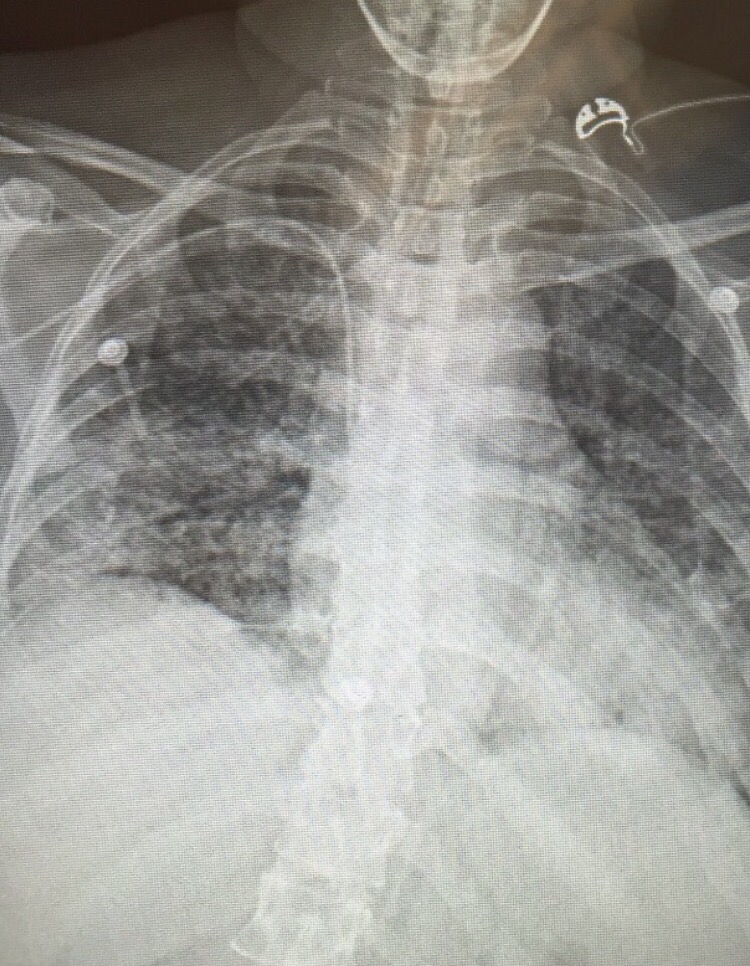

A late middle-aged man with advanced lung cancer was switched to 3-weekly pembrolizumab after his malignancy progressed through multiple courses of chemotherapy. Pet CT at 12 weeks showed stable disease. However, he presented with sudden onset fever, worsening cough, and breathlessness after 6 months of immunotherapy. There was no contact or travel history of note, and clinical examination was remarkable only for mild hypoxia requiring oxygen support, fever of 38.7 degrees Celsius and bilateral basal pulmonary crackles. He did not have a “toxic” appearance. His chest X-Ray is shown below.

The diagnosis was correctly made by Dr. Eugene Lim (in the comment to this vignette), which is hypersensitivity pneumonitis secondary to pembrolizumab. This is a well known adverse effect of the class of cancer drugs known as checkpoint inhibitors. With regards to pembrolizumab, the incidence of pneumonitis is believed to be rare, occurring at approximately 3.8% of a large cohort of patients on the drug. Nonetheless, it is important to quickly recognise the syndrome as therapy is high-dose corticosteroids. There is a tendency in the local setting to view drug-related pneumonitis as diagnoses of exclusion, and to start patients on broad-spectrum antibiotics and/or antivirals first while arranging bronchoscopy and bronchoalveolar lavage – and to start steroids only after infection has been excluded. This delays appropriate treatment and subjects patients to unnecessary antimicrobial agents.

I’ll stick my neck out and call this autoimmune granulomatous alveolitis (or pulmonary alveolar proteinosis, or hypersensitivity pneumonitis, but I think I can see several large granulomas esp left UZ), due to uncontrolled T-helper/cytotoxic activation through PD-1L antagonism.

Treatment is with high dose steroid.

Of course the Resp/ID will balk at this and do bronchoscopic lavage and pan-cultures first. BAL should yield lymphocytes predominant PAS-positive proteinosis.